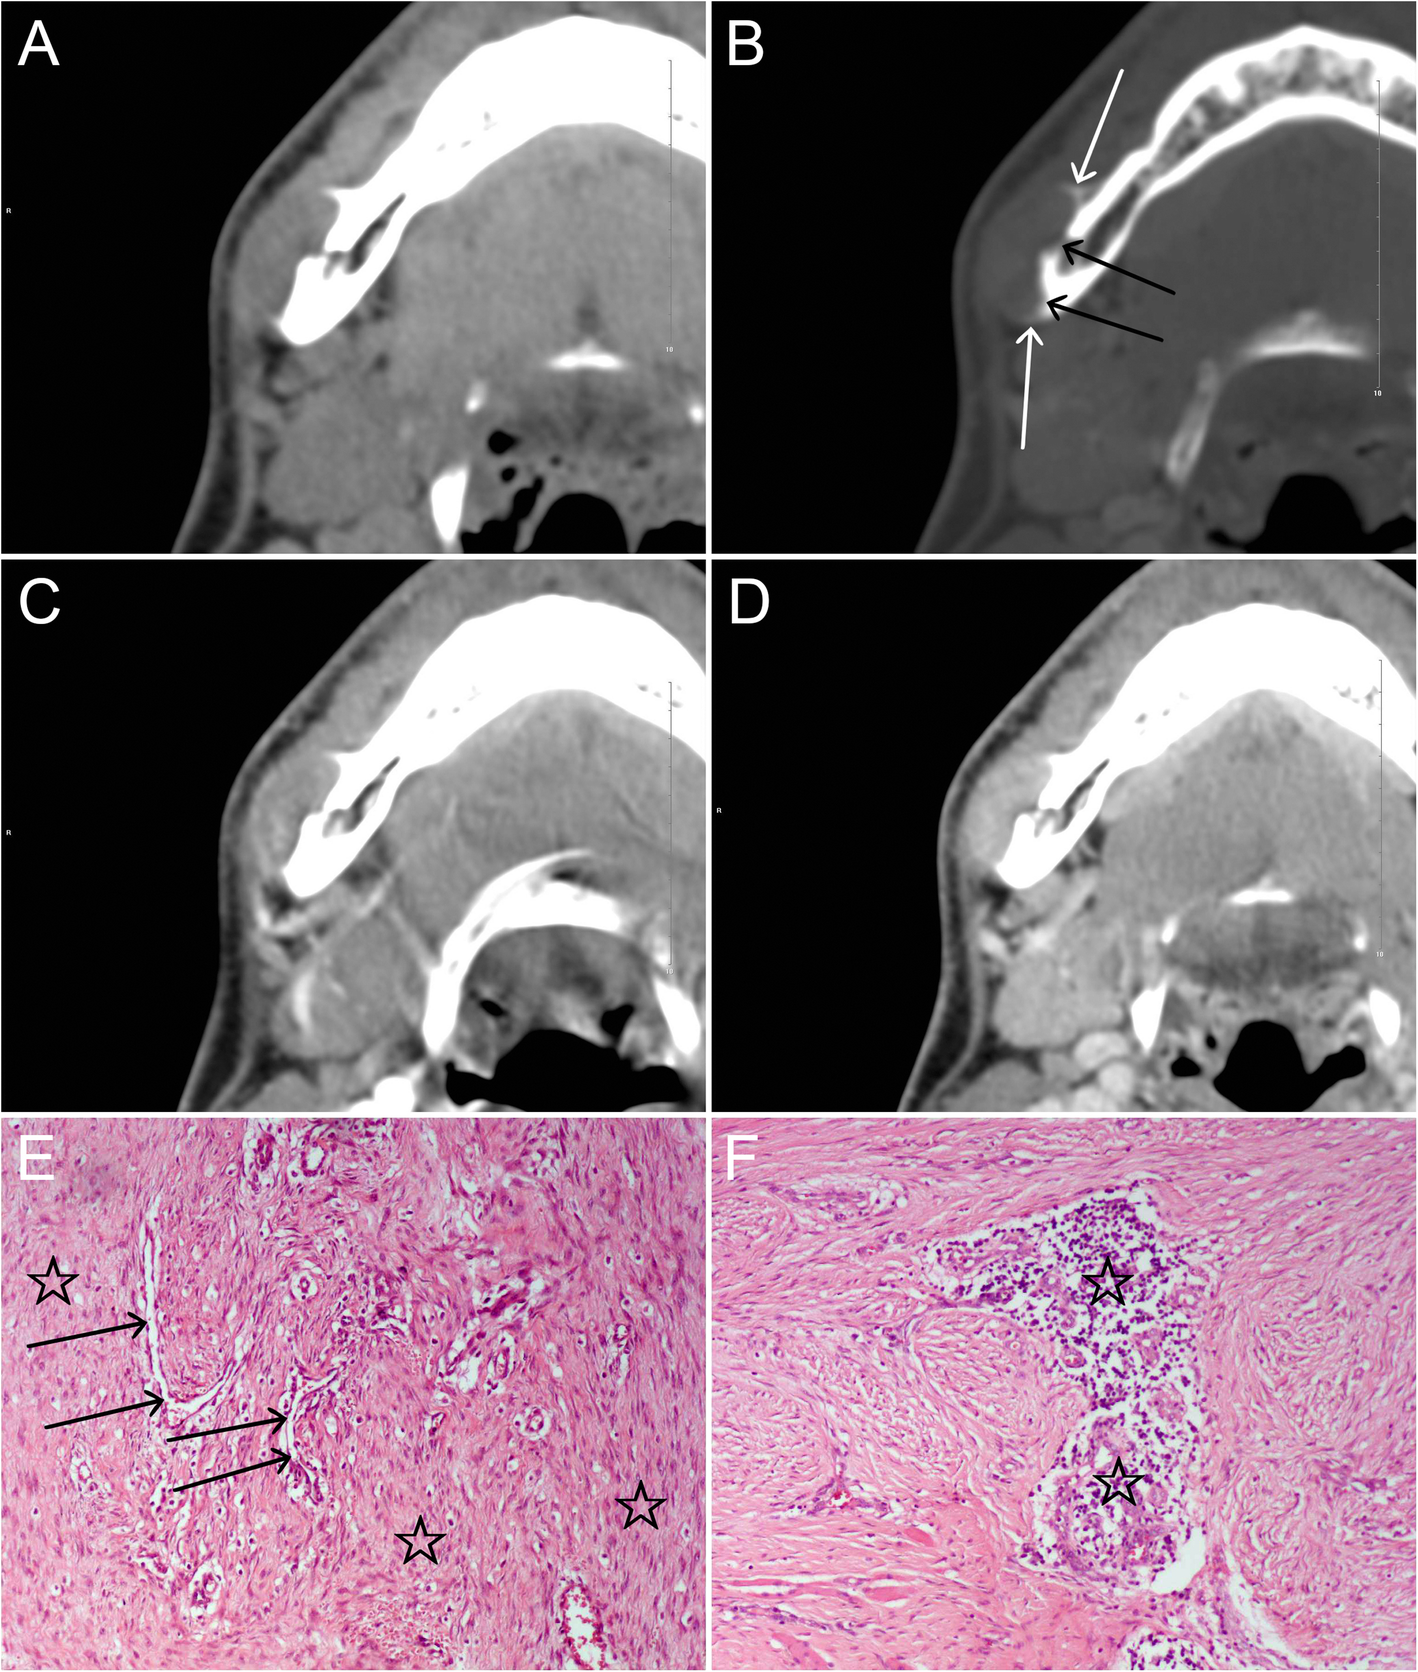

Fig. 1

A young patient in his twenties with a myofibroma in the right body of the mandible. a and b: Axial unenhanced MDCT images show a well-defined round lesion on the lateral margin of the mandible, with periosteal reaction (white arrows) and resorption of the external cortical bone (black arrows). c and d: The lesion shows marked enhancement on axial arterial- and venous-phase contrast-enhanced MDCT images and greater enhancement is seen in the venous phase. e: Photomicrograph (HE, × 100) demonstrates a large number of interlacing bundles of spindle-shaped cells (☆) with tapered blunt-ended nuclei and eosinophilic cytoplasm; hemangiopericytoma-like pattern of the blood vessels (arrows) is focally seen. f: Inflammatory cells (☆) are also present in the lesion (HE, × 100)